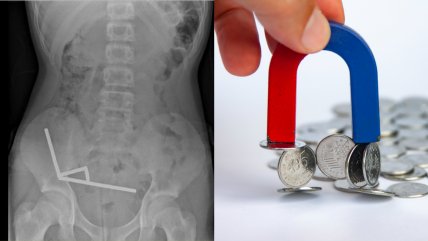

Niño sufrió grave lesión intestinal tras ingerir 100 imanes en Nueva Zelanda